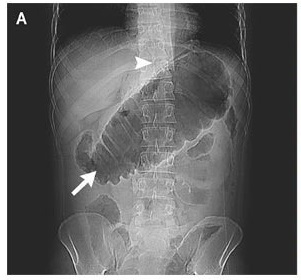

X-Ray of the abdomen showed a severely dilated transverse colon (arrow) and free air (arrowhead).